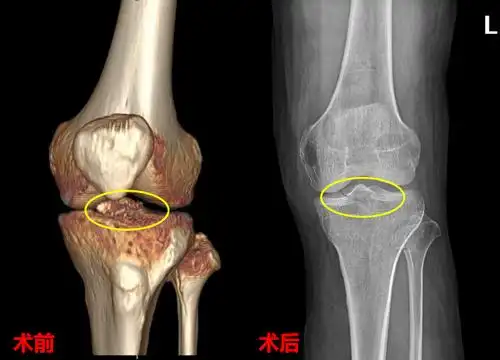

疼痛,肿胀,活动受限,在外院做膝关节x线检查发现是左侧胫骨髁间棘骨折